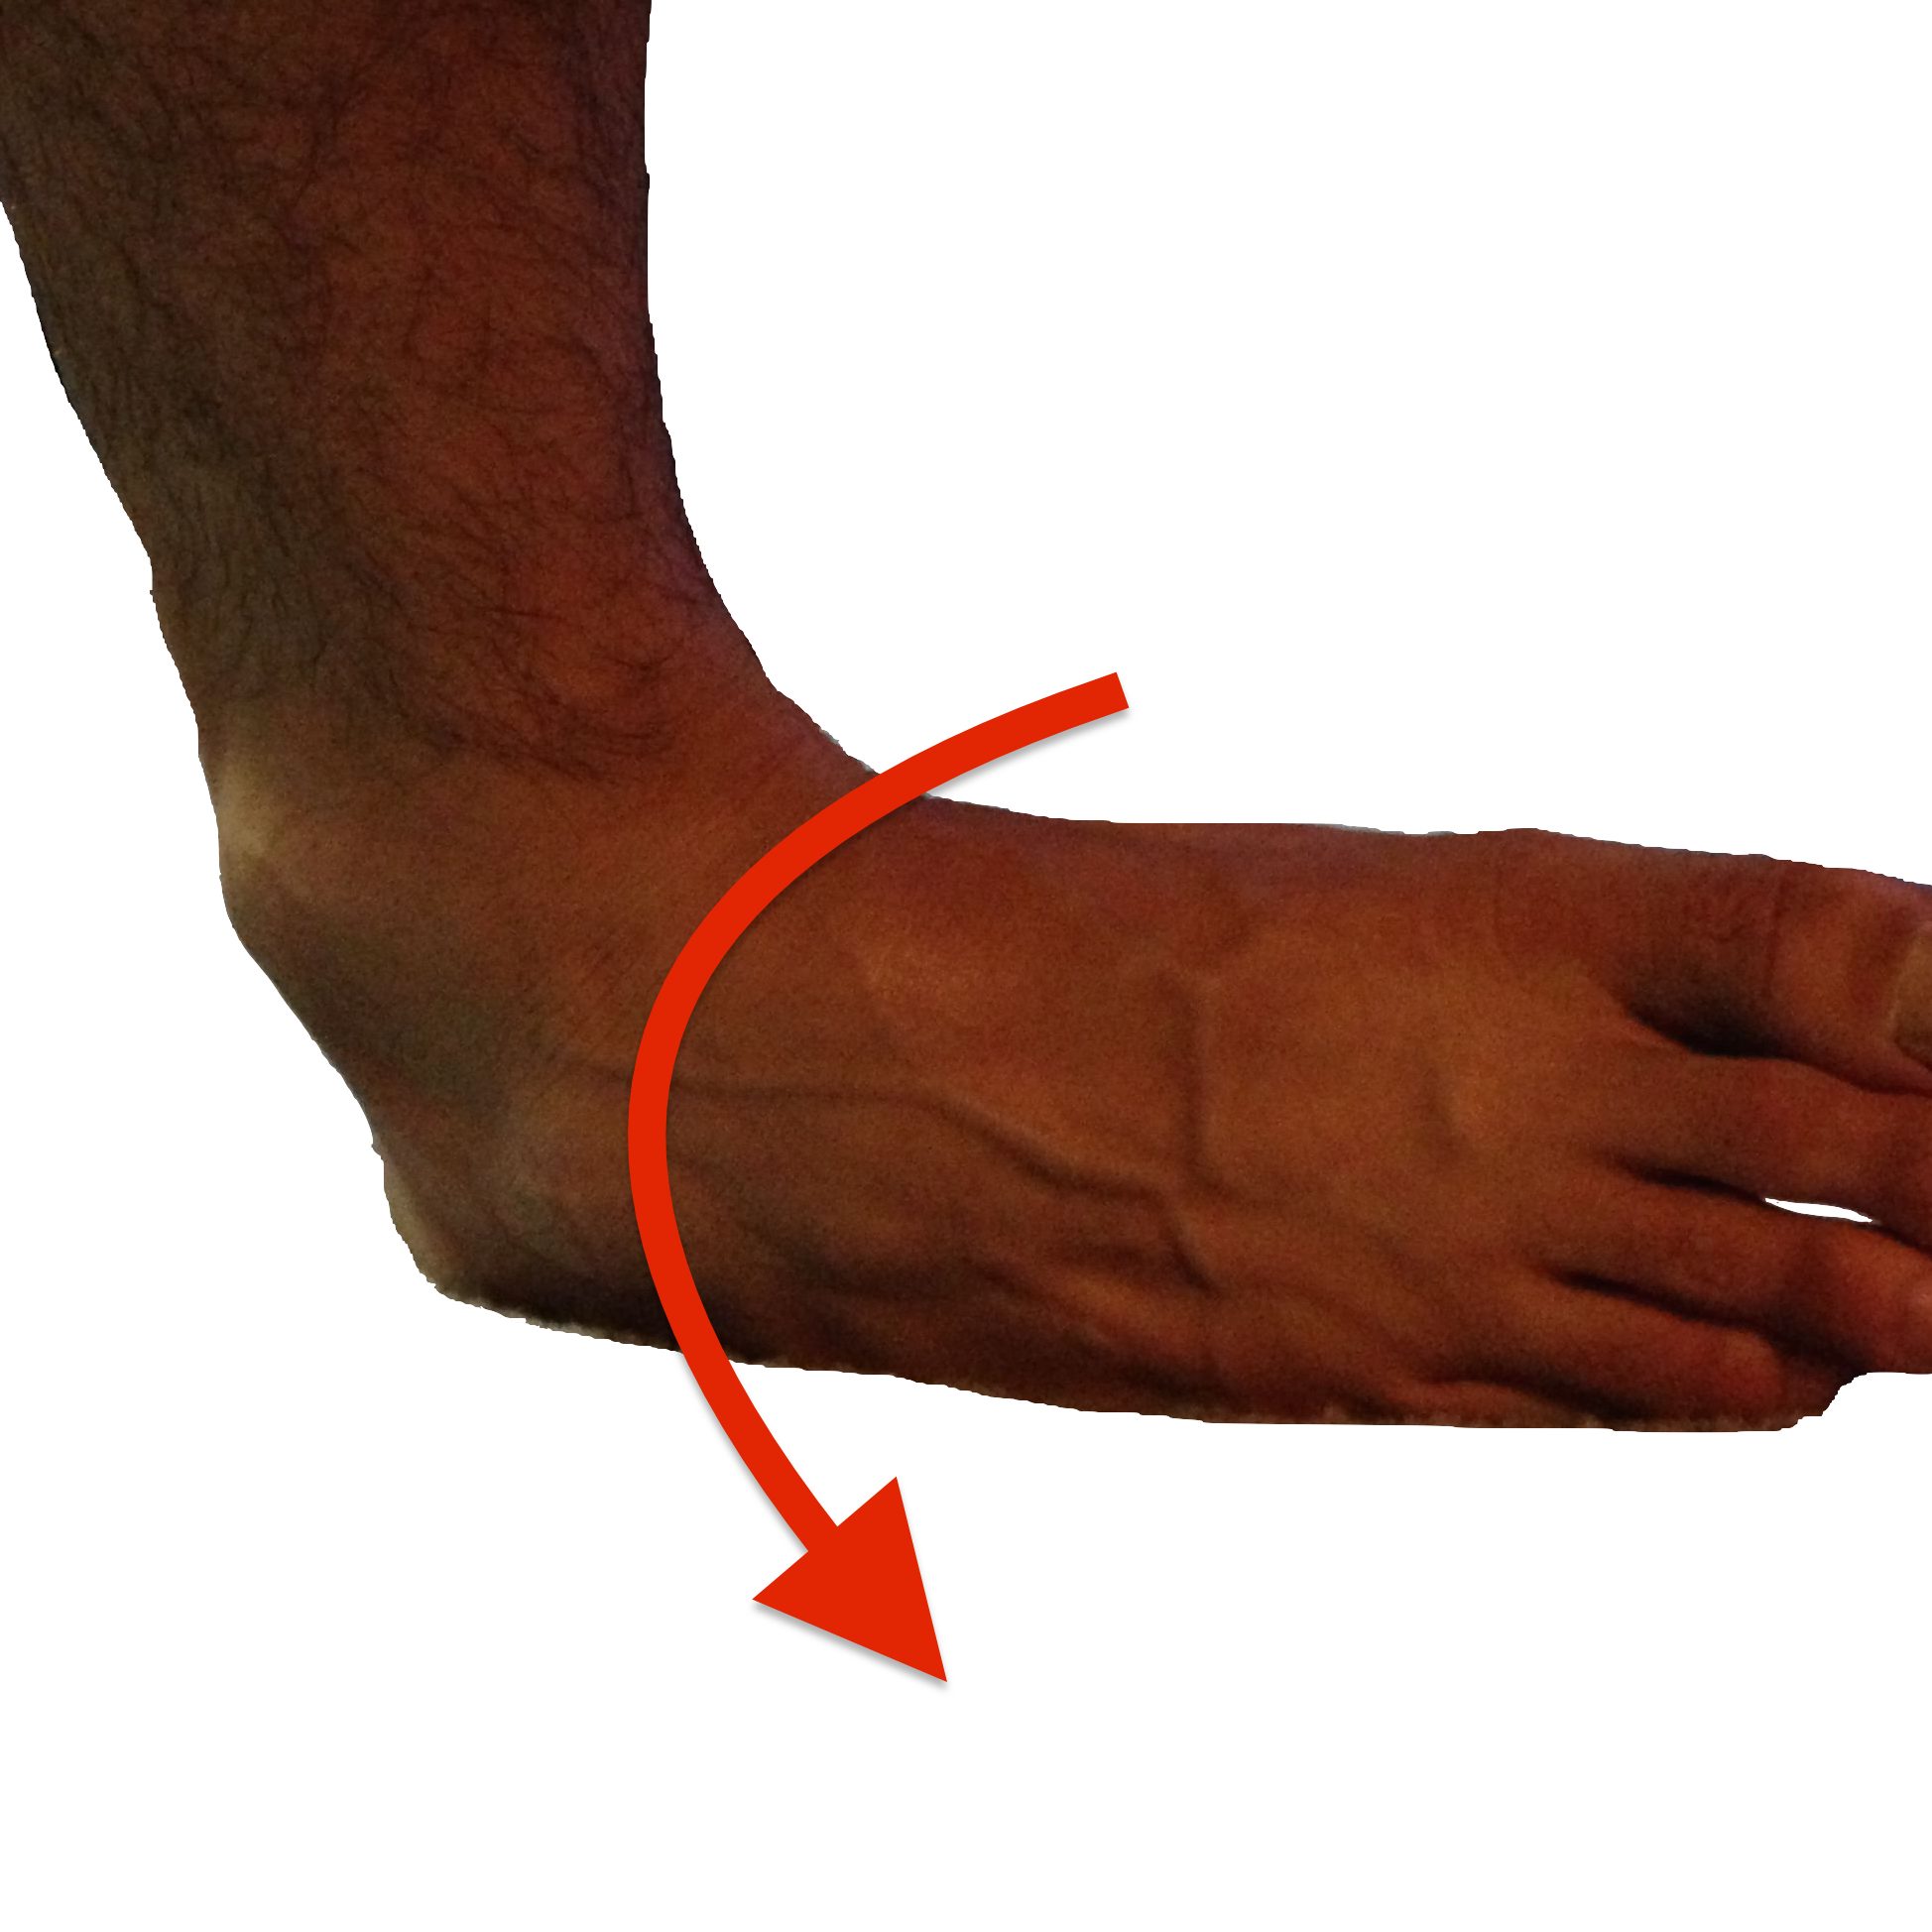

Covering all the common injuries and pain our feet and ankles experience over a lifetime. Click on the links below for more information.